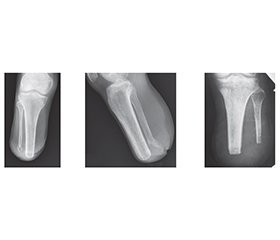

Актуальність. Стресові переломи кісток ампутаційних кукс нижніх кінцівок є недостатньо вивченим ускладненням протезування, що розвивається на тлі порушеного кісткового ремоделювання та повторюваного механічного навантаження. Мета роботи: дослідити клінічні, рентгенологічні й морфологічні особливості стресових переломів кісток ампутаційних кукс нижніх кінцівок і визначити їх зв’язок із термінами й характером протезування. Матеріали та методи. Обстежено 23 пацієнти віком 21–49 років зі стресовими переломами кісток ампутаційних кукс нижніх кінцівок у різні терміни після протезування. Проведено клінічну оцінку больового синдрому й функції ходи, рентгенологічне дослідження з аналізом стану кортикального шару та трабекулярної архітектоніки, а також морфологічне дослідження кісткової тканини за матеріалами ревізійних оперативних втручань; додатково здійснено аналіз системних і локальних факторів ризику розвитку стресових переломів. Статистичну обробку результатів виконували з використанням параметричних методів, рівень статистичної значущості становив p < 0,05. Результати. Встановлено, що ранні стресові переломи (≤ 4 міс. після протезування) формуються на фоні незавершеного структурно-функціонального формування кукси й активного репаративного остеогенезу та у 72 % випадків виникають протягом перших 2,5 місяця, супроводжуючись помірними порушеннями кортикальної та трабекулярної архітектоніки. Переломи цієї групи локалізувалися переважно в зонах максимального механічного навантаження й анатомічної васкулярної вразливості. Пізні стресові переломи (> 4 міс. після протезування) характеризувалися вираженим остеопорозом, гіперостозом, кістоподібною перебудовою медулярного каналу та грубим порушенням трабекулярної структури, що відображало хронічне патологічне ремоделювання кісткової тканини. Двобічна ампутація асоціювалася з прискореним формуванням стресових переломів незалежно від термінів протезування. Висновки. Стресові переломи ампутаційних кукс нижніх кінцівок є наслідком дисбалансу між процесами кісткового ремоделювання й повторюваним механічним навантаженням. Терміни та якість протезування, біомеханіка ходи, а також поєднання системних і локальних факторів визначають характер і темпи розвитку ушкоджень, що обґрунтовує необхідність індивідуалізованого підходу до протезування та поетапного дозування навантаження.

Background. Stress fractures of amputation stumps of the lower extremities are an understudied complication of prosthesis use that develops against the background of impaired bone remodeling and repeated mechanical stress. Aim: to investigate the clinical, radiological, and morphological features of stress fractures of lower limb amputation stumps and to determine their relationship with the timing and nature of prosthetic rehabilitation. Materials and methods. Twenty-three patients aged 21–49 years with stress fractures of lower limb amputation stumps were examined at various times after prosthetic fitting. A clinical assessment of pain syndrome and gait function was performed, as well as an X-ray examination with analysis of the condition of the cortical layer and trabecular architectonics, morphological examination of bone tissue based on materials from revision surgical interventions. Additionally, an analysis of systemic and local risk factors for stress fractures was performed. Statistical processing of the results was made using parametric methods, with a statistical significance level of p < 0.05. Results. It was found that early stress fractures (≤ 4 months after prosthetic fitting) form against the background of incomplete structural and functional formation of the stump and active reparative osteogenesis; in 72 % of cases, they occur within the first 2.5 months and are accompanied by moderate disturbances in cortical and trabecular architectonics. Fractures in this group were localized mainly in areas of maximum mechanical stress and anatomical vascular vulnerability. Late stress fractures (> 4 months after prosthetic fitting) were characterized by severe osteoporosis, hyperostosis, cystic remodeling of the medullary canal, and gross disruption of the trabecular structure, reflecting chronic pathological remodeling of bone tissue. Bilateral amputation was associated with accelerated formation of stress fractures regardless of the timing of prosthetic replacement. Conclusions. Stress fractures of lower limb amputation stumps are the result of an imbalance between bone remodeling processes and repeated mechanical stress. The timing and quality of prosthesis use, gait biomechanics, and a combination of systemic and local factors determine the nature and rate of damage development, which justifies the need for an individualized approach to prosthetic rehabilitation and a phased load dosage.